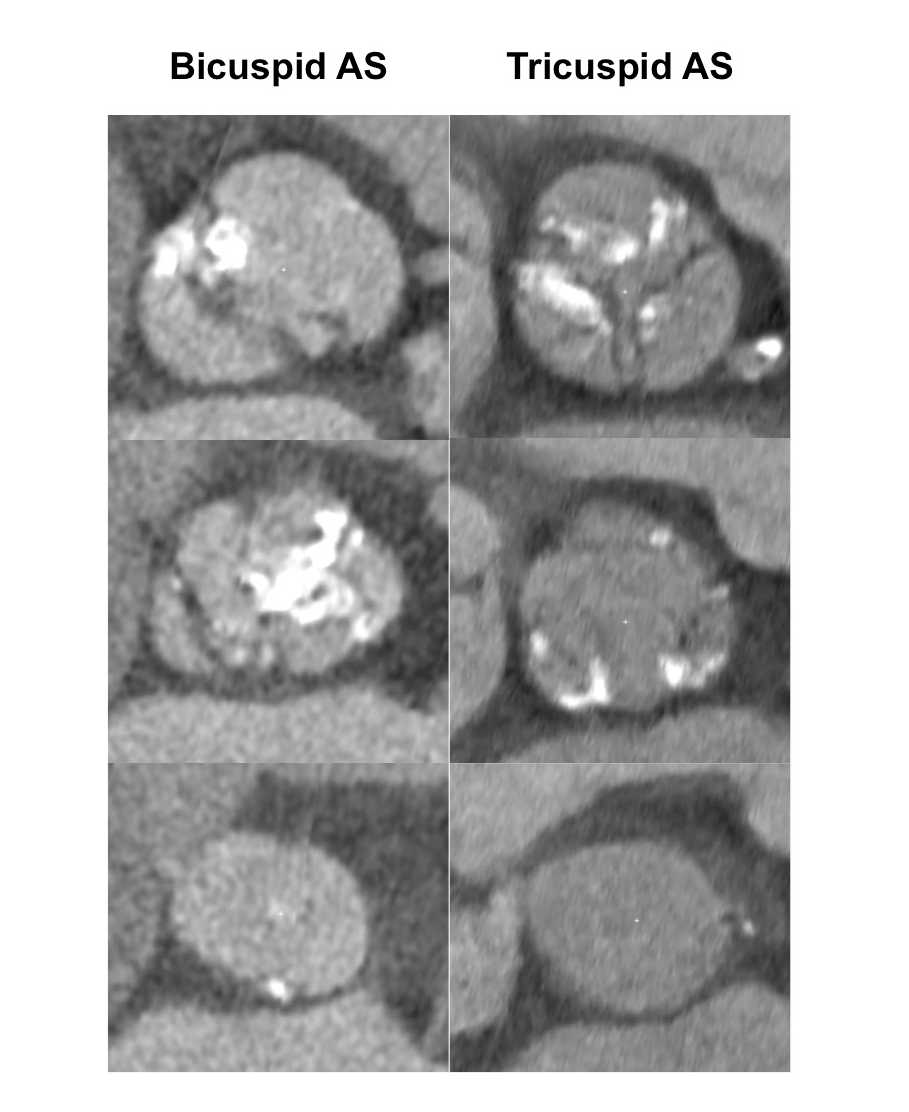

Aortic Stenosis And Bicuspid Aortic Valve